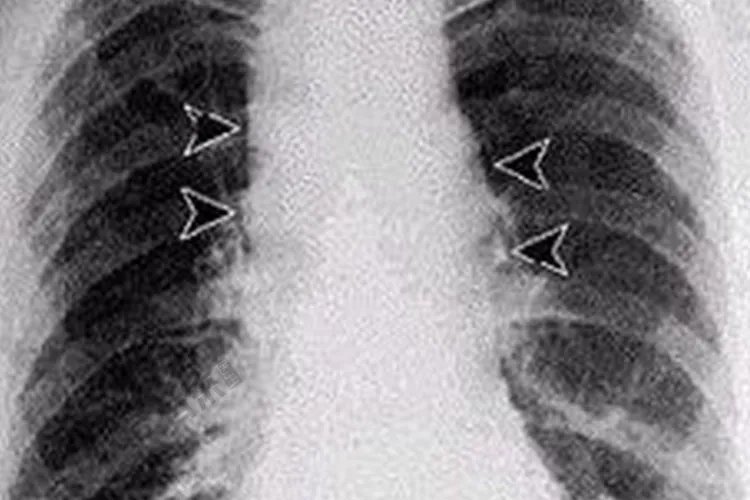

概述肺炭疽患者临床表现主要为短期、非流感样表现,有时可出现水肿。肺炭疽是炭疽的一种类型,可由皮肤炭疽继发而来,需遵医嘱治疗。症状肺炭疽较少见,初起病时类似感冒,临床症状有发热、全身不适、咳嗽、胸闷等,2~4日后好转。重者突然又出现高热、呼吸急促、咳嗽、咯血性痰、胸痛、出汗等重症表现。X线胸片可见相应改变。此外,肺炭疽容易并发败血症而出现感染性休克等,亦有生发炭疽杆菌性脑膜炎者。病情多较凶险。

病因人类炭疽的主要传染源是患病的动物,它们的皮毛、肉、骨粉等均可携带细菌造成传播。炭疽患者的痰、粪便及病灶分泌物可检出细菌具有传染性,但人与人之间的传播极少见。肺炭疽多为原发性,主要通过呼吸道吸入带有炭疽杆菌芽胞的粉尘或气溶胶引起,也可继发于皮肤炭疽。诊断本病可根据患者的病史,如是否生活在存在炭疽的地区,是否从事与畜产品密切接触的职业是否食用过可疑肉制品等,结合患者的临床症状及实验室检查及影像学检查进行疾病的诊断。X线胸片可见纵隔增宽肺部炎症水肿、栓塞和胸腔积液等征象。治疗一般治疗严格隔离患者,对其分泌物、排泄物按芽孢消毒方法进行处理,需对症治疗。不能进食者可予以输液,出血严重者适量输血,有循环衰竭者,进行抗休克治疗。病原治疗青霉素为最有效的抗生素,应及时足量应用。抗血清治疗对重症者可用,应用前必须先作皮试。